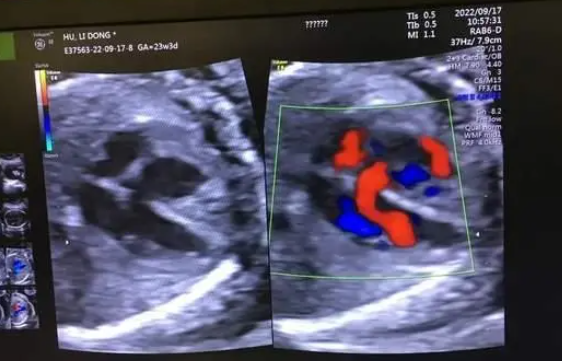

进行胎儿超声颈项透明层厚度(nuchal translucency,NT)检查,该检查利用超声测量胎儿颈后部皮下组织内积液的厚度,测值越大,染色体异常的风险越高。临床研究表明:胎儿NT厚度越高与罹患21-三体综合征、18-三体综合征、13-三体综合征等疾病的风险呈正相比。NT检查时还会检查胎儿的静脉导管(venous catheter,DV)频谱。相关研究显示:胎儿NT增厚及DV血流频谱异常都和先天性心脏病之间存在一定的联系。

(3)第三次:孕20-24+⁶周左右

胎儿系统性超声检查,也就是所谓的大排畸,也称为四维彩超。该检查为孕期超声检查中一个非常关键的步骤,可筛查出九种常见的胎儿发育异常及其他一些重大的结构异常。孕妈妈在进行胎儿系统性超声检查时,一定要在具有产前超声筛查资质的医院或产前诊断机构进行,以保障检查结果的可靠性。